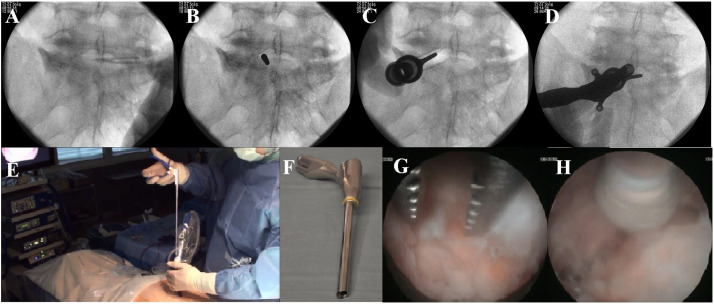

Background: Backache is second most common problem presenting to the primary healthcare providers. Lumbar discectomy has been revolutionized from open conventional discectomy to endoscopic removal. Endoscopic procedures are proving their superiority regarding good outcome, less wound site pain and shorter hospital stay, in Neurosurgery as well. Micro discectomy and Endoscopic discectomy is used only in few centres in Pakistan. This study aimed to share our experience of early surgical outcome endoscopic lumbar discectomy in terms postoperative pain improvement and duration of hospital stay Methods: This prospective study was carried out at Neurosurgery Department, Jinnah Hospital, Lahore from Jan 2014 to Jan 2016. During this period, 35 patients of both sexes, aging between 20 and 60 years, with symptoms and signs of lumbago with sciatica were enrolled. Data was collected on a questionnaire after informed verbal and written consent. Results: A total of 35 patients were operated including 10 males and 25 females. Their age ranged from 20 to 60 years with mean age 33.14±8 years. Majority (32, 91%) of the patients had left side prolapsed paracentral disc, and remaining (3, 9%) had right sided prolapsed disc. Regarding the level of disc 19 (54%) patients had L45 while 15 (43%) had L5-S1 and remaining one (2.9%) patients had L3-4 level. The post-op wound site visual analogue score was 1.57±1.1. Twenty-five patients had VAS of 1 (71.4%). Minimum hospital stay was 1 day in 16 (45.75%) patients and maximum was 4 days in 3 (8.6%) patients. Mean hospital stay was 1.83±0.95 days. The only complication encountered was iatrogenic dural tear seen in one patient but with no CSF leak from wound site. No surgical site infections were reported at follow-ups.

Conclusion: Endoscopic Lumbar discectomy is a safe procedure with short hospital stay.